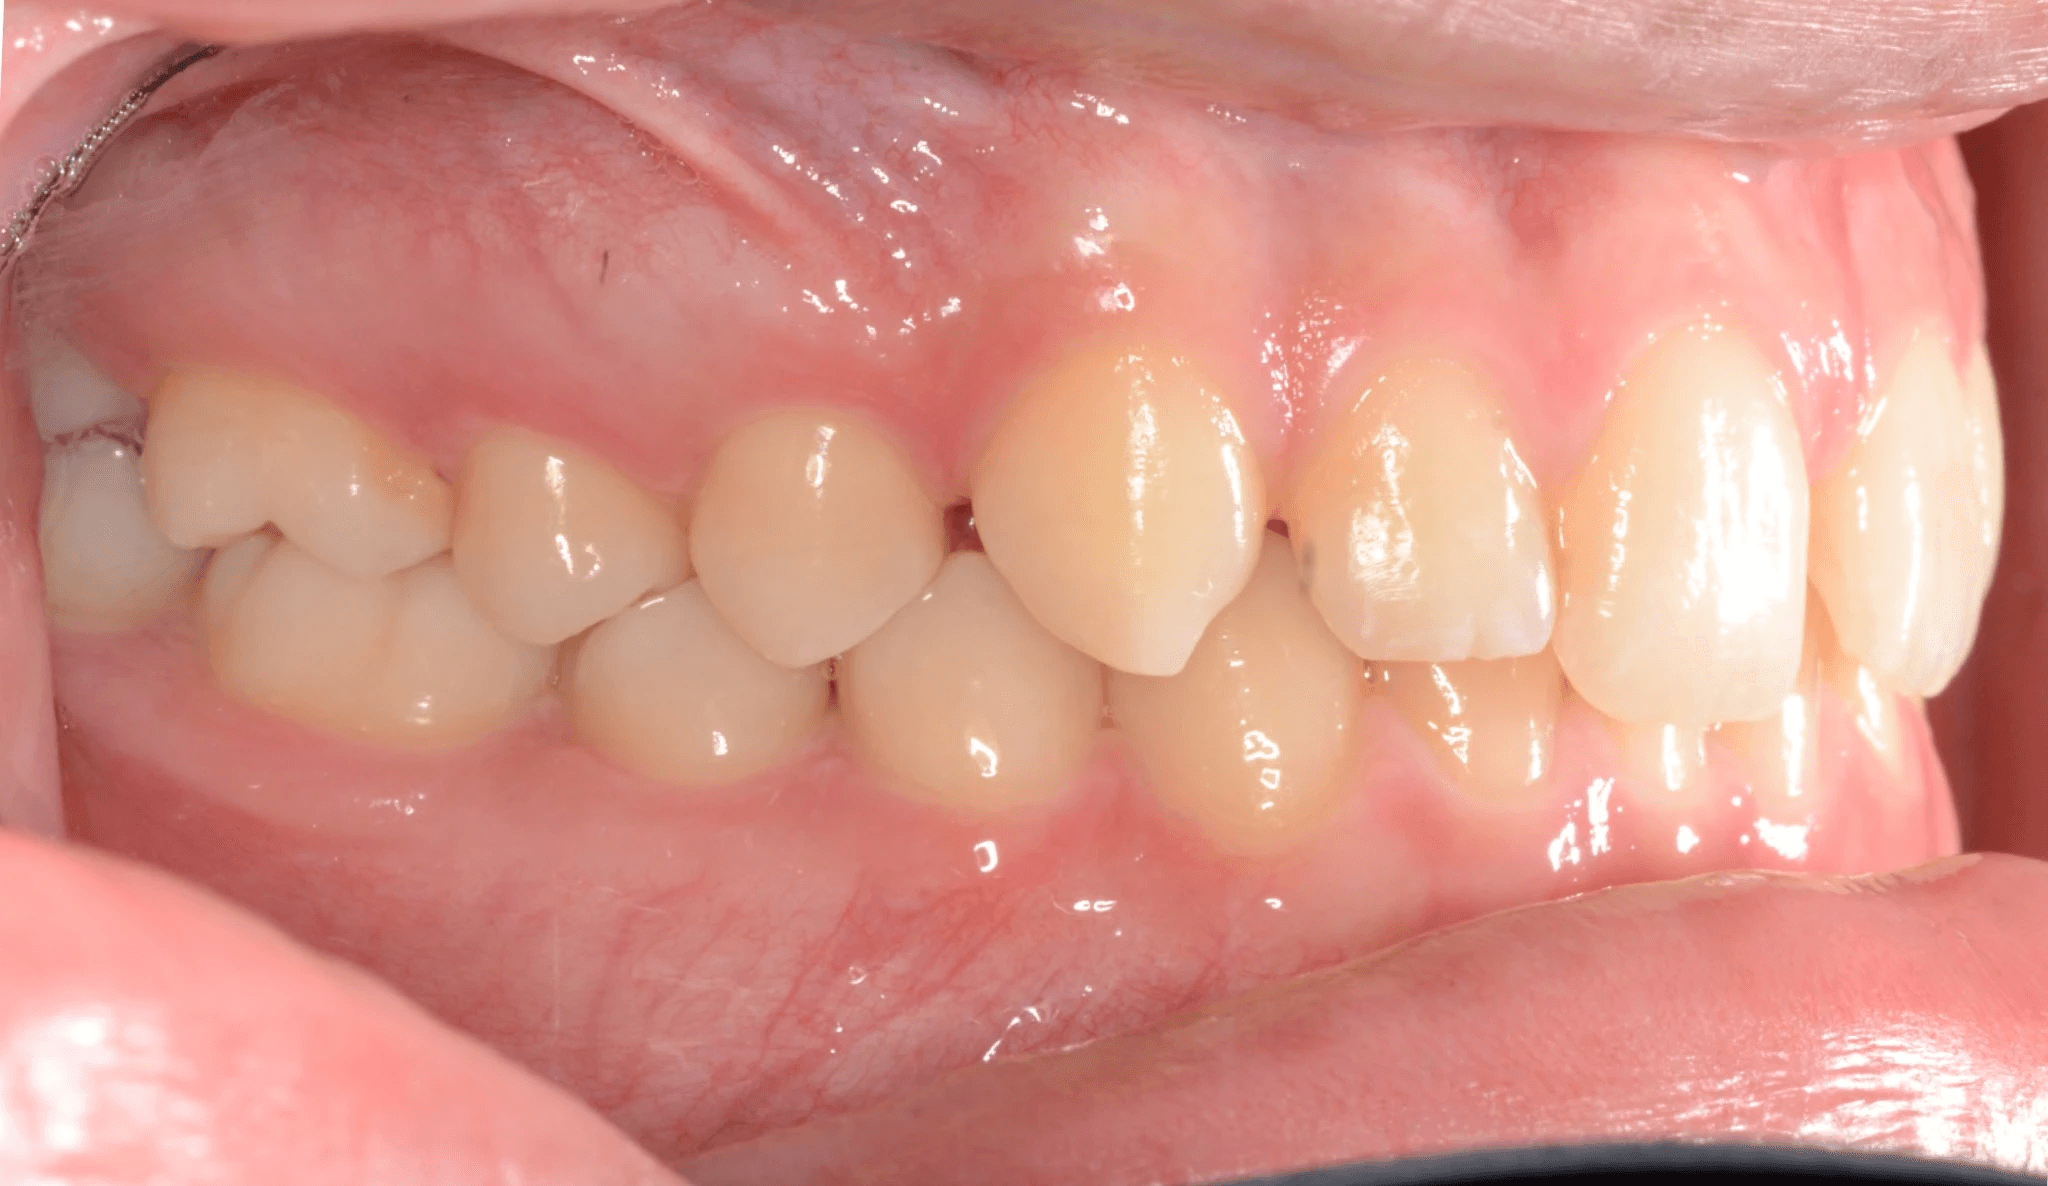

Final results

INTRAORAL